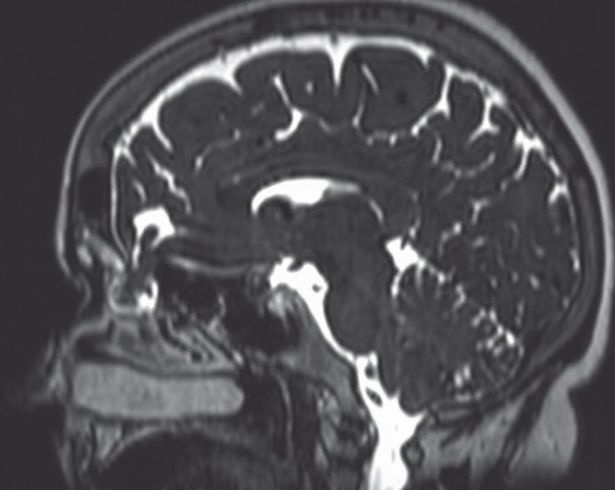

Οι γιατροί σε μια προσπάθεια να καταλάβουν τι ακριβώς συμβαίνει έβαλαν μια μικροκάμερα στη μύτη και ανακάλυψαν την τρομακτική αλήθεια.

Τα οστά του κρανίου στο σημείο εκείνο ήταν σπάσει ελαφρώς με αποτέλεσμα τα εγκεφαλικά υγρά να τρέχουν στην μύτη.

Οι γιατροί είναι βέβαιοι πως το πρόβλημα προέκυψε αμέσως μετά το τεστ κορονοϊού ενώ για ευνόητους λόγους δεν δόθηκαν στην δημοσιότητα ούτε το όνομα της ασθενούς, ούτε όμως και του νοσοκομείου.